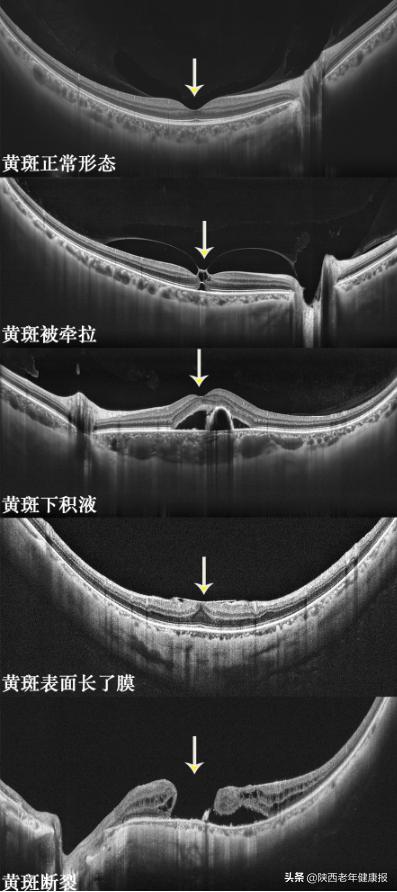

常见的黄斑病变有:年龄相关性黄斑变性、近视性黄斑变性、中心性浆液性脉络膜视网膜病变、黄斑水肿(糖尿病性视网膜病变、视网膜静脉阻塞等引起)、黄斑前膜、黄斑裂孔、玻璃体黄斑牵拉综合征等。需要药物或手术治疗以争取最大限度保护视功能。